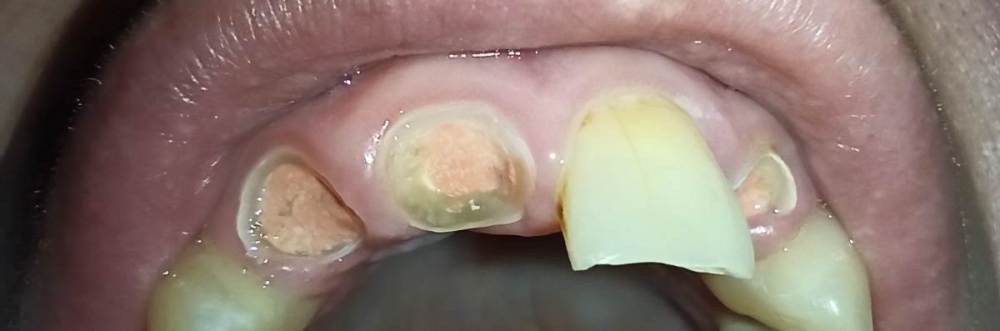

IvanIvan Опубликовано 28 декабря, 2023 Автор Поделиться Опубликовано 28 декабря, 2023 @Notherbrick , фото приложил. Рентген смогу днем прикрепить. Ссылка на комментарий

Notherbrick Опубликовано 29 декабря, 2023 Поделиться Опубликовано 29 декабря, 2023 Эти корни лучше удалить. Ссылка на комментарий

Doc Опубликовано 1 января, 2024 Поделиться Опубликовано 1 января, 2024 Гарантийной такая работа не будет. Еще снимки нужно смотреть, но, скорее всего, эти корни не будут стоить вложенных в них средств. Если для вас деньги не играют серьезной роли, то чисто для души можно попробовать эти зубы отпротезировать и посмотреть сколько простоят. А вдруг продержатся! Ссылка на комментарий